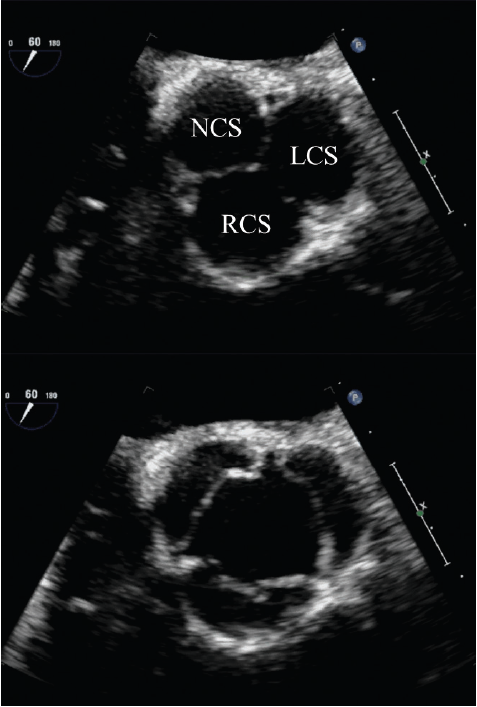

Echo Assessment Of Aorta And Aortic valve - Basic echo

2 Ascending Aorta Sino tubular junction Sinuses of Valsalva Aortic annulus Aortic valve • Appearance –Cusps –Closure line –Vegetations –Annulus ... Read Here